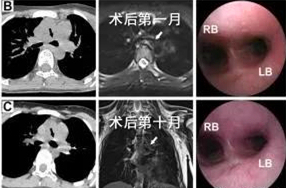

图3.术后随访中患儿胸部CT及气管镜检查

确定治疗方案后,胸外科医疗团队立即联系我院3D打印研究中心曹铁生教授和西安交通大学贺健康教授,首先利用我院自主研发的3D打印机为患儿制作了1:1气管模型,充分评估病情特点,然后为患儿量身定做了可降解的聚己内酯(PCL)外支架。2018年1月初,黄立军副主任为患儿施行了手术,术中在软化的气管外放置了PCL支架,挡开了来自左肺动脉干和胸主动脉的挤压,手术仅耗时1小时15分。术后连续对患儿随访观察10个月,患儿塌陷的左主支气管已完全复张,PCL支架也逐渐降解吸收,患儿术后1月开始上学,回归了正常的生活。